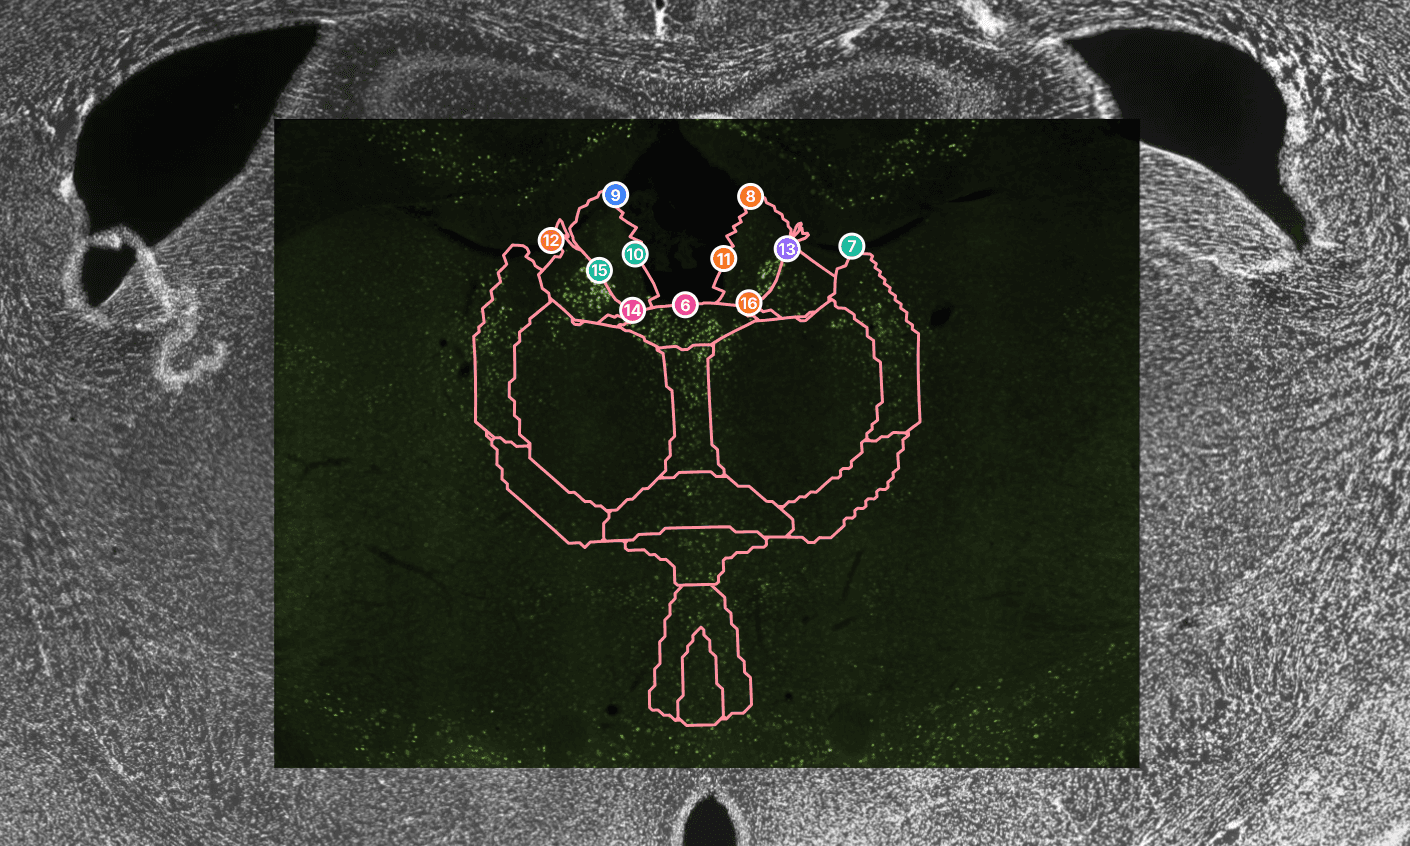

Automated mouse brain atlas registration from a single 4x DAPI overview with precise 10x or 20x detail-image alignment.

NeuroQP turns one 4x DAPI whole-slice overview into a complete brain atlas registration that supports your whole study. Your 10x or 20x detail field is then placed on top of the registered 4x slice, and quick manual refinements keep the local alignment accurate. Since the entire atlas is available, you can update brain region selections later without redoing the registration process.